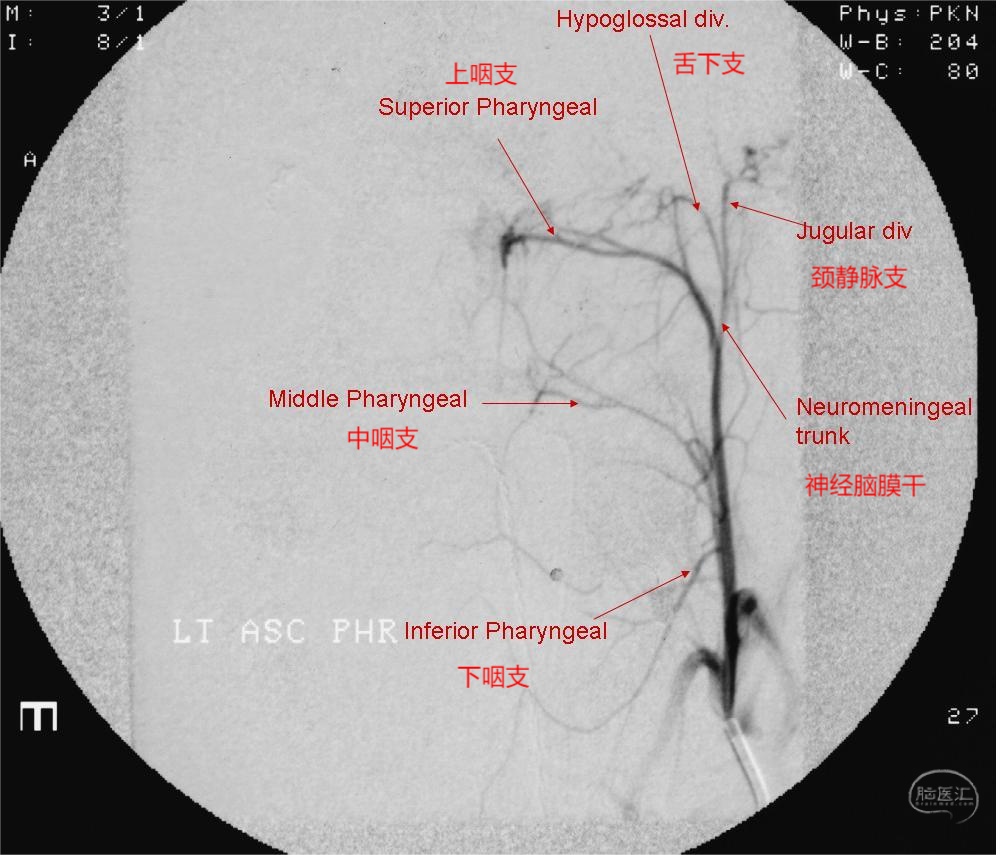

图1 咽升动脉一般情况下是颈外动脉发出的第一或第二个分支,侧位示其在颈外动脉和颈内动脉之间向上走形于咽部后外侧。

图11 咽升动脉超选造影经典DSA图像。血管某支可以是一支也可以是数支或一丛,是根据解剖位置和供血区域而定。例如下咽支不是指仅仅一支血管,而是位于此区域内的一支或一丛血管均为下咽支。